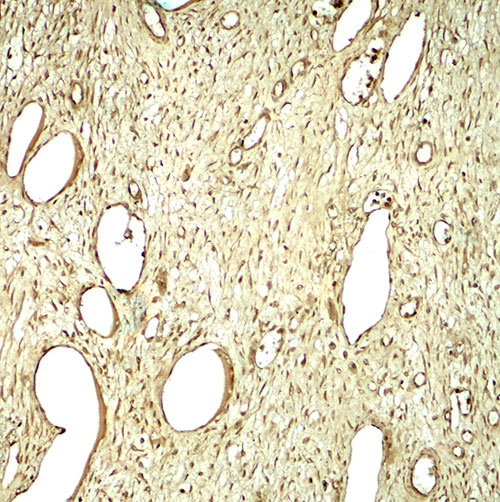

Immunohistochemistry of SLC29A1 in human ovary tissue with SLC29A1 antibody at 5 μg/mL.